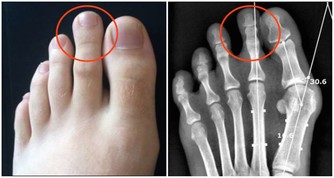

1. 你的頭髮掉得厲害

硒的重要作用之一是幫助T4甲狀腺激素轉化為更活躍的形式T3,如果缺硒,你可能患有甲狀腺功能減退症,其中之一就是脫髮。